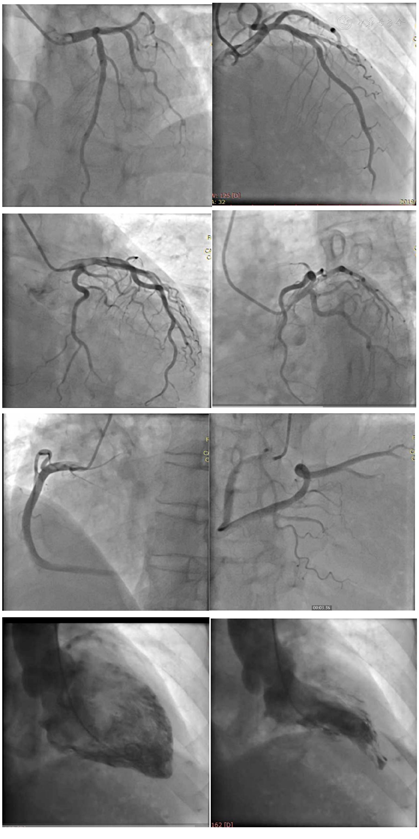

前降支:斑块,慢血流;回旋支右冠状动脉:慢血流;心尖部运动略减弱(图13)。